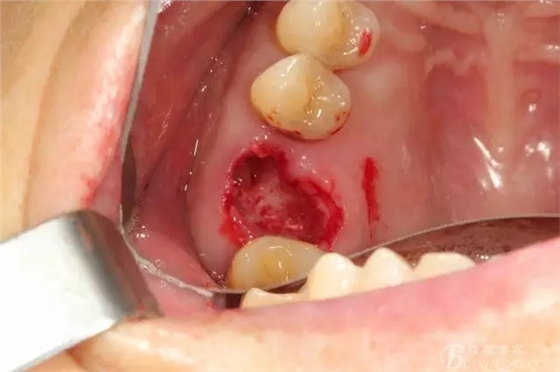

清理拔牙窩 清理的非常干凈包括齦緣周圍牙齦適當(dāng)修整后看到拔牙窩是巨大的,牙槽中隔已經(jīng)吸收

備洞只是稍微修整就可以,因?yàn)閷?shí)在太大了也沒啥好讓我們折騰的骨頭了

備洞的時(shí)候當(dāng)然想盡一切辦法讓顎側(cè)骨頭往頰側(cè)推,使得種植體的頰側(cè)有人為做出來的骨壁